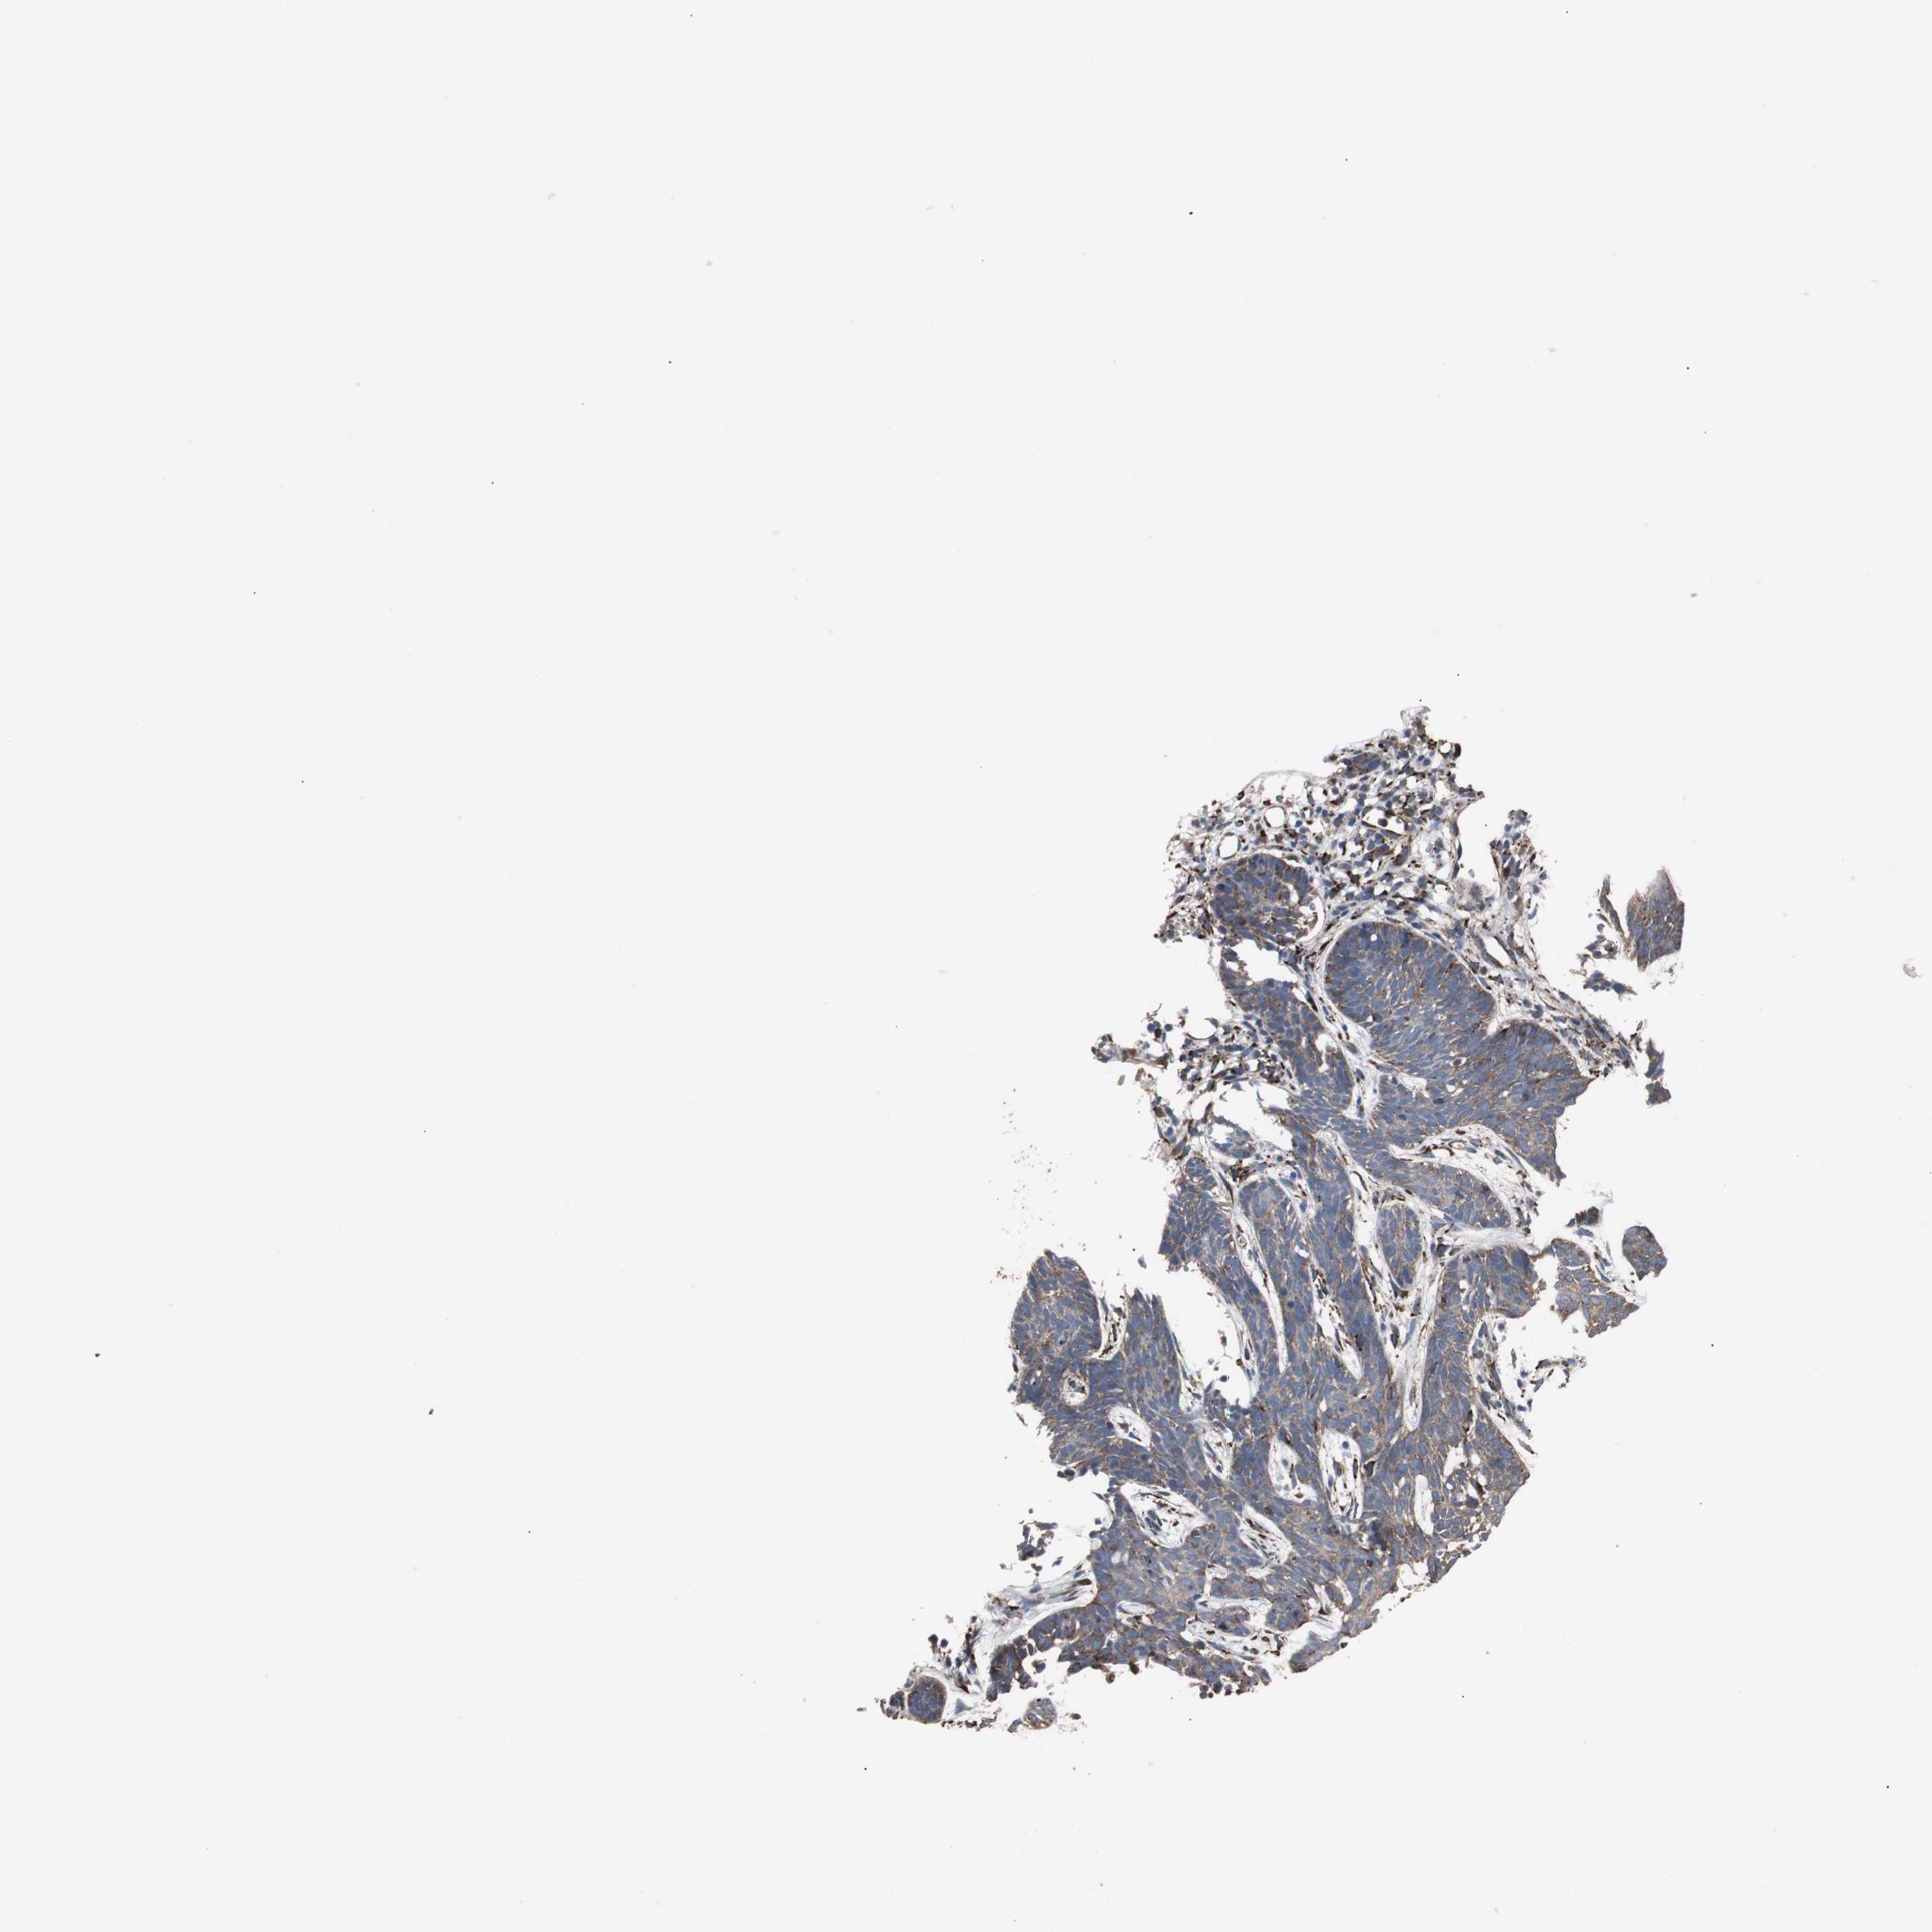

SKIN CANCER - Protein expressioni

A mouse-over function shows sample information and annotation data. Click on an image to view it in a full screen mode. Samples can be filtered based on level of antibody staining by selecting one or several of the following categories: high, medium, low and not detected. The assay and annotation is described here.

Each image is clickable and will lead to virtual microscopy that enables deeper exploration of all samples and also displays staining intensity scores, fraction scores and subcellular localization as well as patient and tissue information for each sample.

Antibody HPA006018

Staining

High

Strong

Quantity

Location

Squamous cell carcinoma, NOS

Basal cell carcinoma